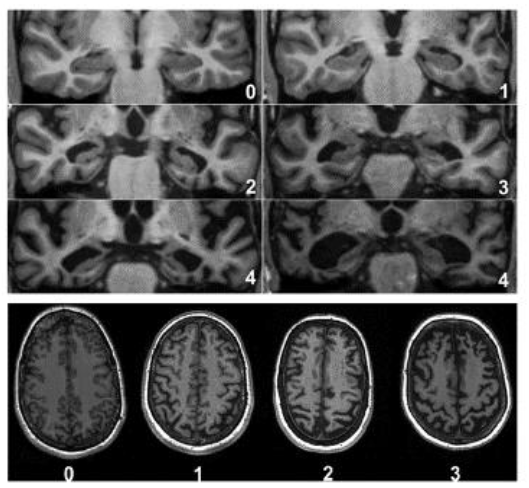

CT、MRIによる形態画像診断では、脳の萎縮、脳梗塞・脳出血、脳腫瘍、水頭症、慢性硬膜下血腫などの有無を調べます。 アルツハイマー型認知症では、脳の全般的萎縮と海馬(矢印部分)の萎縮(脳溝拡大、脳室拡大、側脳室下角拡大など)が著明である。 連載第11回で示したものは水平断で、ここでは冠状断を示した 本書で紹介している治療法等は、著者が臨床例. 近畿大学病院放射線診断科で認知症に対する画像検査を受けられた患者様・ご家族の皆様・・・ お知らせ 近畿大学病院放射線診断科(以下、当科)では、「認知症患者の診療情報を用いた認知症患者データベースの構築」という臨床研究を行っています。. 認知症ドッグで軽度認知症を早期発見して適切な対策を行うことにより、症状の進行を阻止することが可能となり、認知症の症状が最後まで出ずにすむケースもあります。 検査内容 1心理学的検査(認知力・記憶力) 2mri検査.

海馬回旋遅滞症は②の冠状断像で最も診断しやすくなります。 海馬のmriを撮影するのは、主にてんかんやけいれんを起こした場合です。 ところが、海馬回旋遅滞症でてんかんを合併するのは10%前後に過ぎません。 発達障害の脳を説明するic理論とは?. 認知症のの診断診断に用に用用いるいる画像 CT MRI SPECT PET •脳血管性病変のの評価評価 •多発性のもの •大大きいものきいもの •両側性のもの •PVLのの評価評価 •小小さなさな病巣のの判定判定 •海馬のの評価評価 •PVHのの評価評価. 5.認知症のセルフチェック 『認知症の人と家族の会』が作成した認知症早期発見テストを試してください。いくつかの項 目が当てはまるなら、ぜひ、認知症外来を受診してください。他の病気と同じように認知症も 早期発見・早期治療が大切です。.

海馬のmri脳画像診断